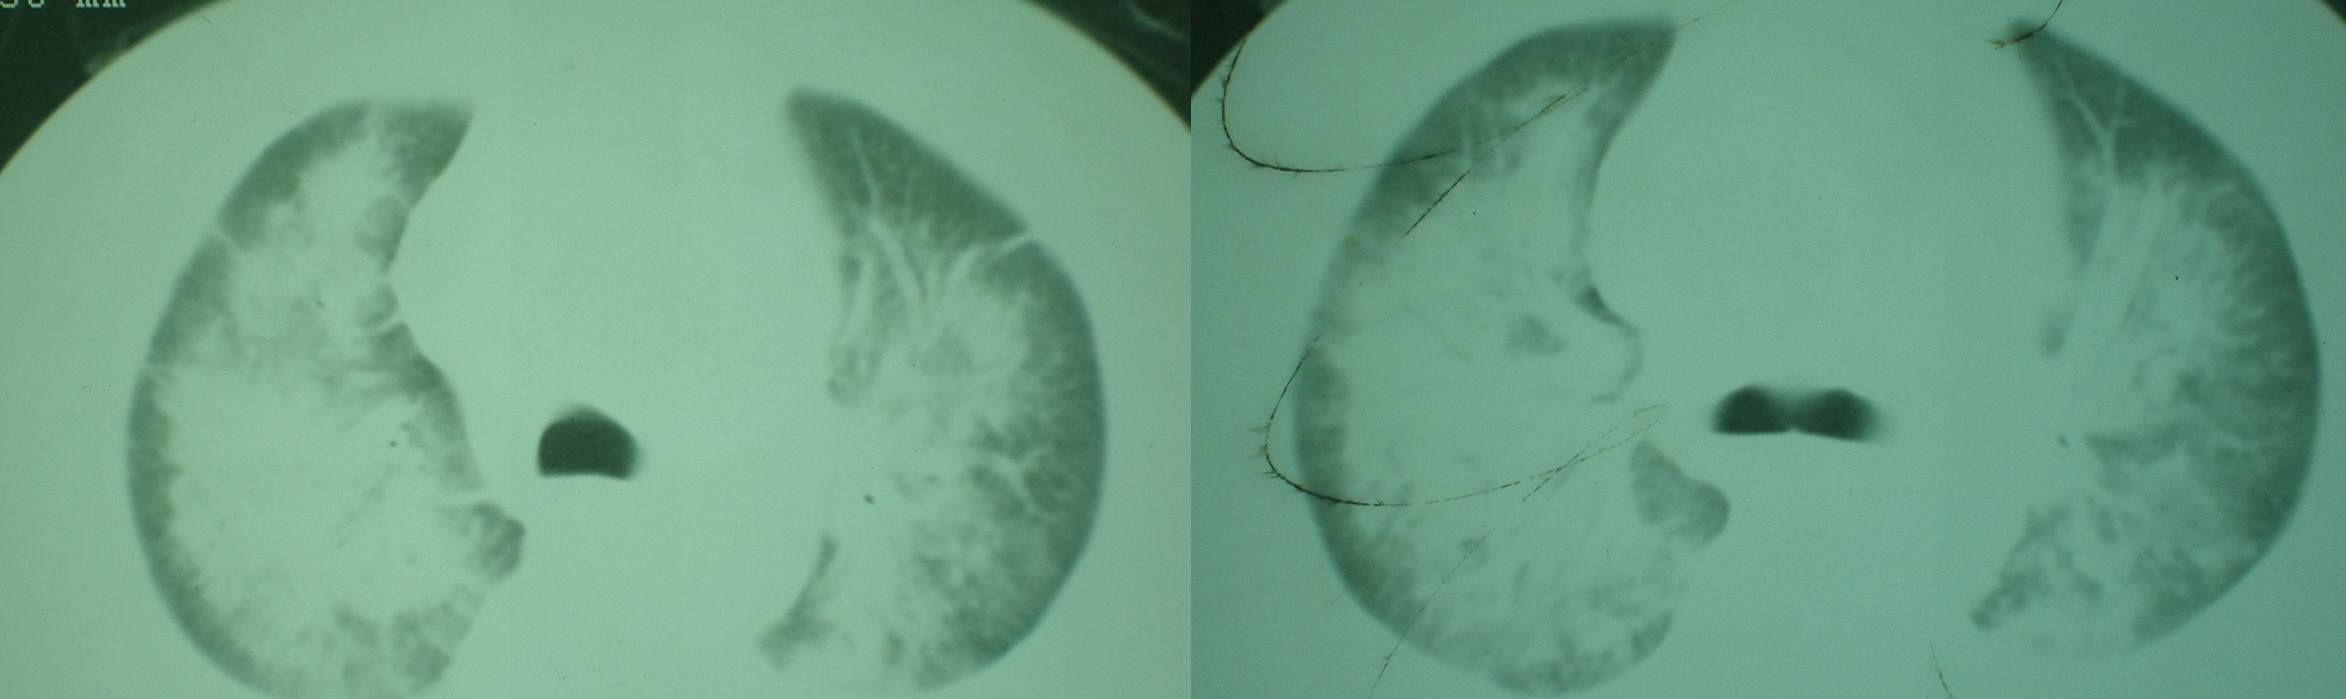

2008年11月18日今天的ct片

2008年9月18日ct片

2008年9月8日ct片: